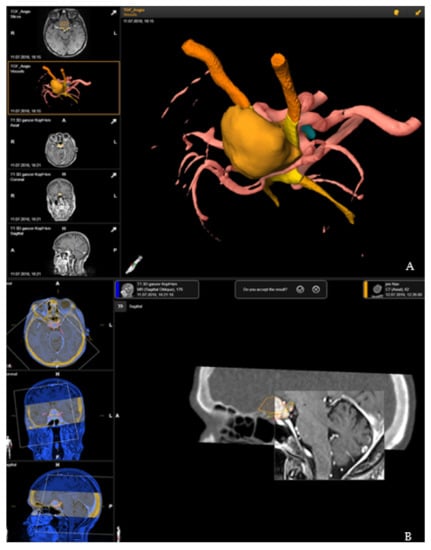

Segmentation of the tumor was usually performed in the T1-weighted post-contrast MRI modality, manually or using autosegmentation with an anatomical mapping element (Brainlab). Brainlab was used to delineate the optic nerves, chiasm, ventricles, pituitary gland or brain stem with unique colors being assigned to each object, and with additional manual segmentation for correction of the automatic segmentation and for segmentation of tumor and risk structures. For segmentation of the vascular risk structures, contrast-enhanced T1-weighted magnetic resonance imaging (MRI), time-of-flight (TOF) MRI angiography or computed tomography (CT) angiography was used and then rigidly registered. Rigid registration was performed by an image fusion element (Brainlab, Munich, Germany). This 3D data set formed the basis for patient registration [7] (Figure 1).

Rigid registration of the preoperative plan with the registration CT scan was performed by image fusion software, Brainlab elements (Brainlab, Munich, Germany). Accuracy of the fusion was checked by a spy-glass feature, with visualization of the preoperative images in an insert of the intraoperative CT, which was moved around for detection of registration failure in all views with appropriate anatomical landmarks (Figure 1).

Figure 1. Preoperative planning and image fusion for 67-year-old female patient with suprasellar meningioma (patient no. 19). (A) Visualization of the tumor (ochre), optic nerves and tract (orange) and optic chiasms (yellow) as a 3D object following segmentation in T1-weighted post-contrast magnetic resonance imaging (MRI) and time-of-flight (TOF) MRI angiography. (B) Rigid fusion of computed tomography scan with T1-weighted MRI scan.